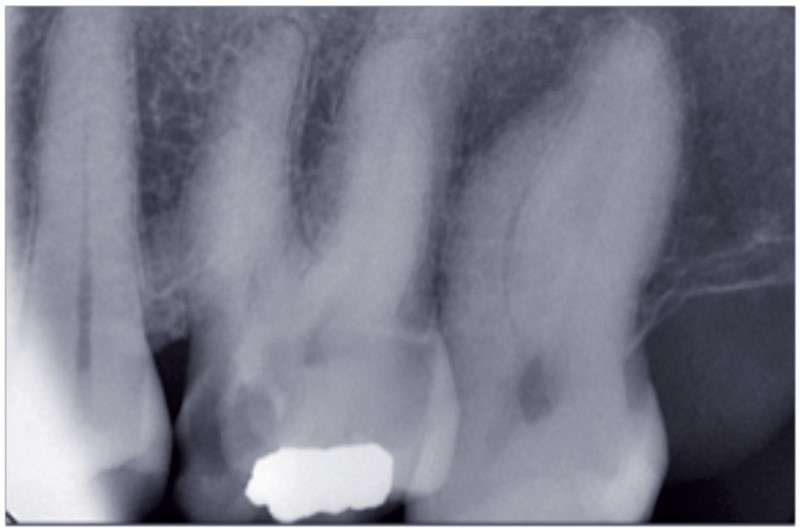

La radiographie rétroalvéolaire est un geste complémentaire lorsqu’elle est réalisée au cours ou à la fin d’un autre acte clinique, pour contrôler l’exécution de ce dernier. L’exemple le plus courant est celui du cliché effectué pendant une extraction délicate ou à la fin de celle-ci.

• Pour une telle radiographie, la CCAM prévoit le code HBQK061 et le libellé « Radiographie intrabuccale rétroalvéolaire et/ou rétrocoronaire d’un secteur de 1 à 3 dents contiguës, perinterventionnelle et/ou finale, en dehors d’un acte thérapeutique endodontique », avec 3,99 € comme tarif de responsabilité de l’Assurance maladie.